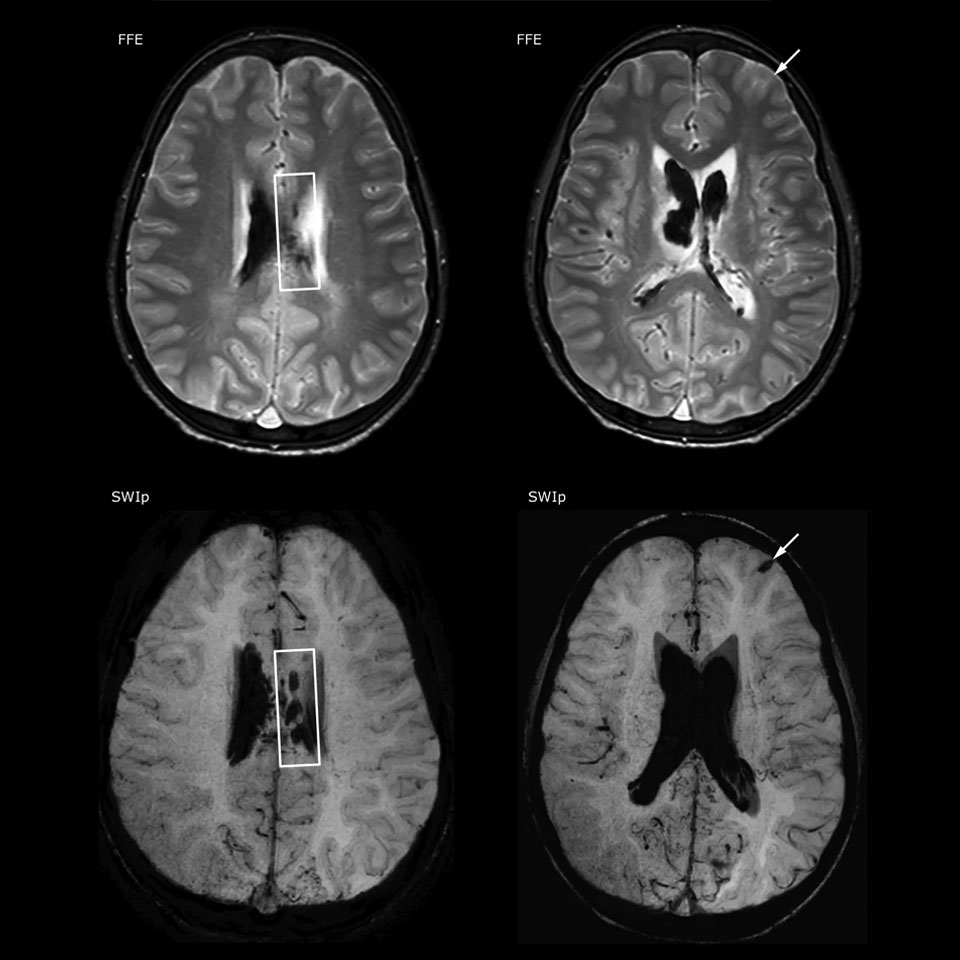

The value of susceptibility weighted imaging in visualizing brain injury is well documented. The Philips multi-echo SWIp technique provides fast susceptibility weighted imaging with enhanced susceptibility contrast and high resolution.

“Pediatric imaging is not without its challenges,” Dr. Miller says. “Since our patients are often very small, we need very high-resolution imaging. In cases of brain injury, we need to obtain information quickly so the treating clinicians can make decisions on care. We rely on high resolution and robust imaging capabilities, and SWIp provides that.”

“SWIp helps us identify blood or blood products, calcification, and diseases that affect the vascular system,” says Dr. Miller. “In children with traumatic brain injuries, it highlights areas that are injured, better than some of the previous techniques that we were using. These children often have micro-injuries that cause small amounts of blood or tissue damage. Adding SWIp helps us to better characterize the extent and nature of the injury. Having characterized an injury to the extent of what’s possible supports our diagnostic confidence.”

Full adoption after initial comparison

“I would definitely recommend other users to implement SWIp. We initially added the SWIp sequence following a lot of support for its utility in the literature. Then we directly compared SWIp to the 2D gradient echo sequences that we were using. After a good amount of clinical experience in seeing its benefits, we were confident to replace the old sequences with SWIp. It gives us a better assessment of the physiological processes of the brain that were less apparent on our previous imaging sequences,” says Dr. Miller. “SWIp is now a routine sequence for imaging traumatic brain injury patients at PCH, and it’s episodically added for patients who have intracranial vascular abnormalities.”

“I believe SWIp is rapidly becoming the standard in imaging traumatic brain injury, because of its high sensitivity to venous blood products. SWIp may even help attract patients; our neurosurgeons often ask to have the patients imaged on our scanners with highly sensitive techniques like SWIp. There’s also a growing application of SWI sequences in other vascular abnormalities because of the possibilities around physiological assessment of the brain than just a standard structural imaging.”